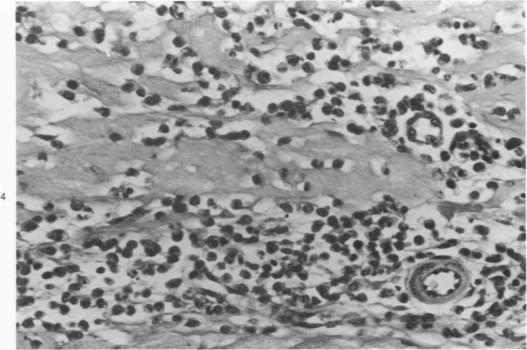

Macrophage-chemotactic factors were extracted from delayed hypersensitivity skin lesions induced by bovine gamma-globulin in guinea pigs. The most active factor, MCFS--1, was highly purified and found to be a heat-labile protein with a molecular weight of 150,000 and to possess in vivo as well as in vitro activity. This factor was homogeneous during polyacrylamide gel electrophoresis, and the chemotactic activity was associated exclusively with this band. Further characterization revealed that its isoelectric point was 6.7 to 6.9 and made a single arc in the beta-globulin region with rabbit antiserums against guinea pig serum on immunoelectrophoresis. This factor seemed to be antigenically different from immunoglobulin G (IgG) by immunodiffusion and immunoadsorption. On the other hand, the chemotactic activity of MCFS-2 was adsorbed by neither anti-IgG nor anti MCFS-1 and that of euglobulin fraction was partially adsorbed by anti-IgG. These indicate the presence of at least three types of antigenically different chemotactic factors for macrophages in the extracts of delayed hypersensitivity skin lesions.

巨噬细胞趋化因子是从豚鼠中由牛γ球蛋白诱导产生的迟发型超敏皮肤损伤中提取的。最具活性的因子MCFS - 1经过高度纯化,发现是一种热不稳定蛋白,分子量为150,000,具有体内和体外活性。该因子在聚丙烯酰胺凝胶电泳中呈均一性,趋化活性仅与该条带相关。进一步的特性分析表明,其等电点为6.7至6.9,在免疫电泳中与兔抗豚鼠血清在β球蛋白区域形成单一弧线。通过免疫扩散和免疫吸附,该因子似乎在抗原性上与免疫球蛋白G(IgG)不同。另一方面,MCFS - 2的趋化活性既不被抗IgG吸附,也不被抗MCFS - 1吸附,而优球蛋白组分的趋化活性部分被抗IgG吸附。这些表明在迟发型超敏皮肤损伤提取物中存在至少三种抗原性不同的巨噬细胞趋化因子。